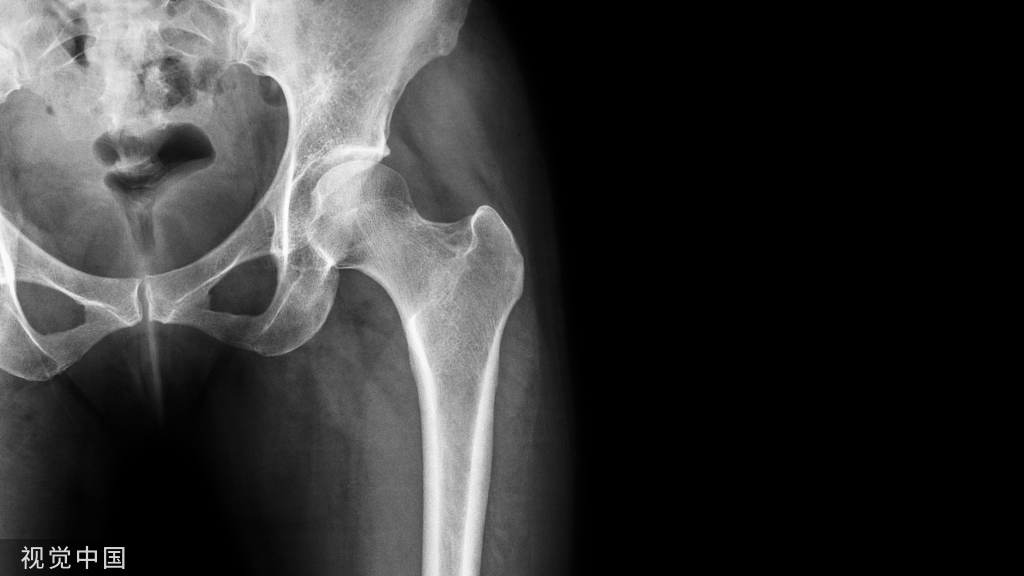

对骨科医生而言老年人股骨转子间骨折始终是很有挑战性的外科手术。由于患者骨质疏松,内固定把持力降低导致手术失败率高。

同时,老年人合并症多,导致骨折后一年的死亡率几乎达到1/3,术后只有20%左右的患者能恢复到受伤前的状态。这些都导致老年髋部骨折成为全球性的重大经济负担。

目前主流的转子间骨折治疗方法是髓内钉固定。提到髓内钉内固定,在此提供一些有用的技巧和方法,目的是使髓内固定获得更好的结果。(仅是个人观点,如有讲的不对的地方还希望各位战友批评指正!)